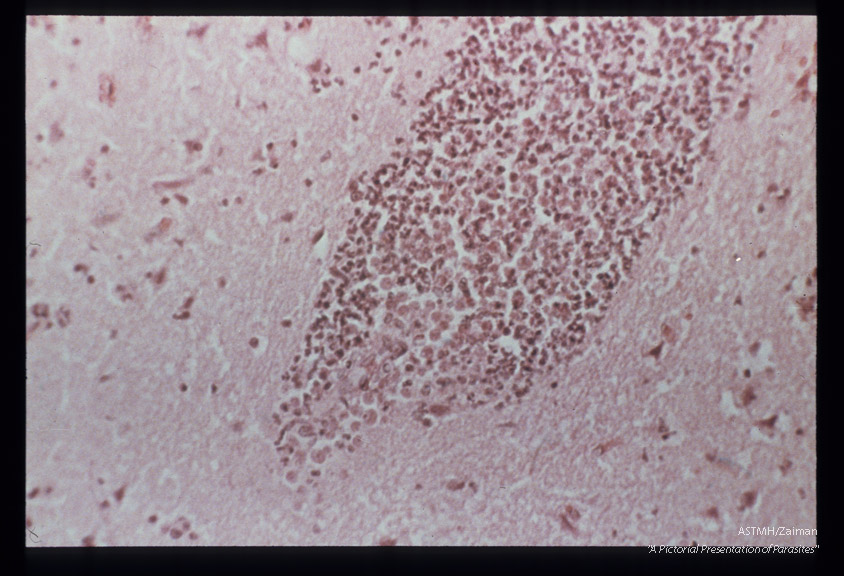

Meningitis- Hematoxylin-eosin stained section of human brain at various magnifications.

Acanthamoeba

Description: Meningitis- Hematoxylin-eosin stained section of human brain at various magnifications.